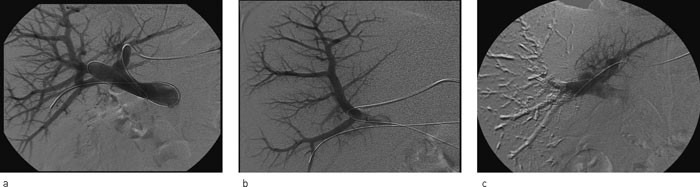

Antall prosedyrer har økt siden starten i 2002, og i 2006 ble sju pasienter embolisert. I alt 77 pasienter fikk utført leverreseksjon det året. Vellykket portveneembolisering ble initialt observert hos 16 pasienter (fig 2), to trengte ny prosedyre. Disse to var blitt embolisert med coiler og polyvinylpartikler. Begge ble embolisert på nytt med lim. En pasient måtte laparotomeres samme dag grunnet intraabdominal blødning. Aksidentell punksjon av leverarterien ble påvist og suturert. En annen pasient hadde forbigående gallelekkasje etter aksidentell punksjon av gallegang. Denne ble behandlet med endoskopisk anlagt stent i gallegangen og et perkutant eksternt dren mot subhepatisk beliggende væskeansamling. Tre andre pasienter fikk lette symptomer, som forbigående feber og abdominalsmerter.

Hos alle våre pasienter ble den planlagte leverresten større etter portveneembolisering. To pasienter måtte gjennom to emboliseringer før ønsket resultat ble oppnådd. Dette skyldtes inkomplett embolisering. Det er imidlertid ikke klarlagt om bruk av partikler gir dårligere embolisering enn hvis man bruker lim (6). Sannsynligvis er det viktig å bruke samme teknikk og samme agens over tid. Vi observerte komplikasjoner hos tre av de 18 pasientene (17 %), de fleste hadde lette, forbigående plager. To av komplikasjonene skyldtes aksidentelle lesjoner ved forsøk på kanylering av en portvenegren. Median liggetid etter portveneembolisering var likevel bare ett døgn.